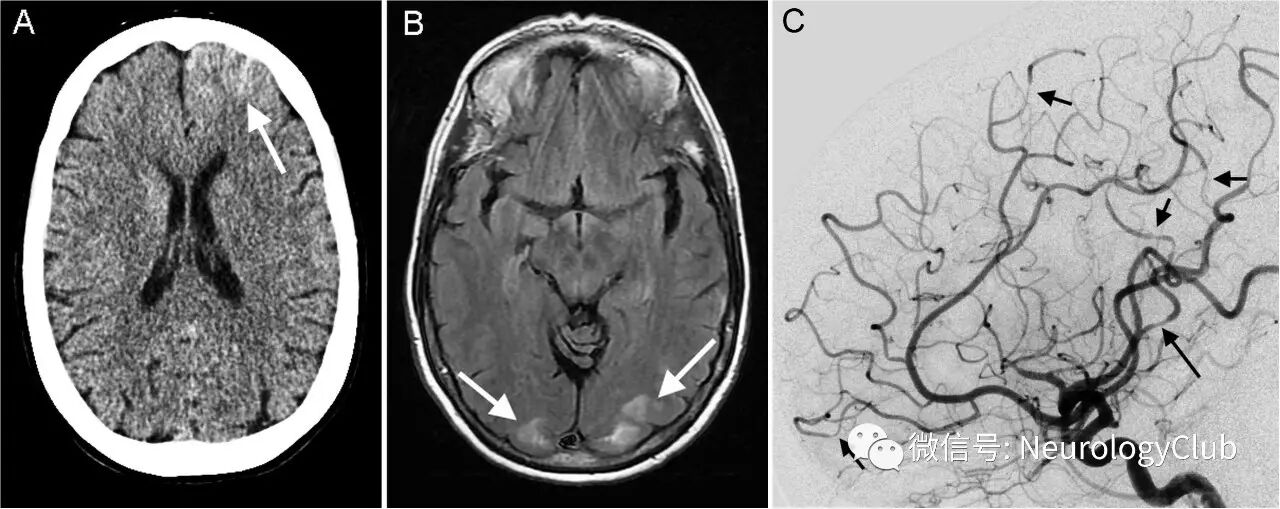

患者入院当天行头颅CT和MRI检查,第二天行脑血管造影(图1)。

(图1:A:CT;B:FLAIR;C:左侧颈内动脉脑血管造影)

头颅CT可见左侧额叶较小范围的凸面蛛网膜下腔出血(cSAH)(图1)。CT血管造影无殊(未放图)。MRI可见双侧顶枕叶T2/FLAIR高信号,可符合可逆性后部脑病综合征(PRES)(图1)。脑血管造影提示多灶短节段狭窄,主要见于左侧大脑前和大脑中动脉的远端皮质支(图1)以及左侧小脑上动脉近端和多处其他血管支配区(图2)。未见动脉瘤或血管畸形。